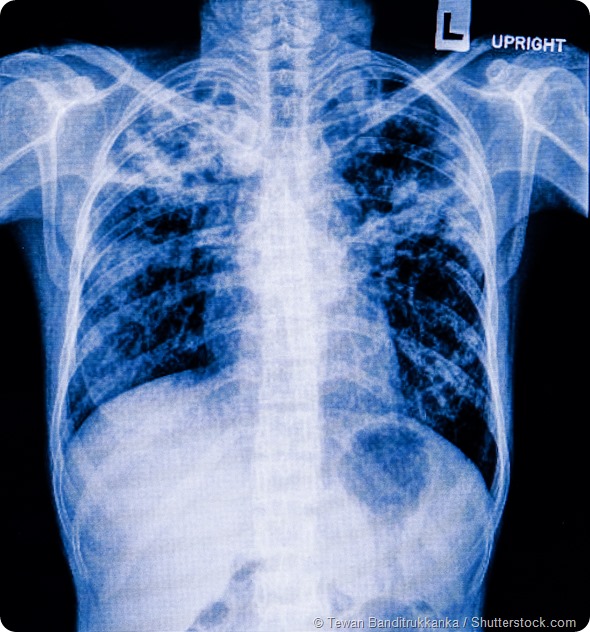

Pneumonia patients x-ray film

Subsequently, there’s been a shift to looking at what exactly is happening to our host immunity that's causing us to be susceptible. What our immune system is doing in relation to influenza that's making us more susceptible to bacterial pneumonia has been the real focus of my research.